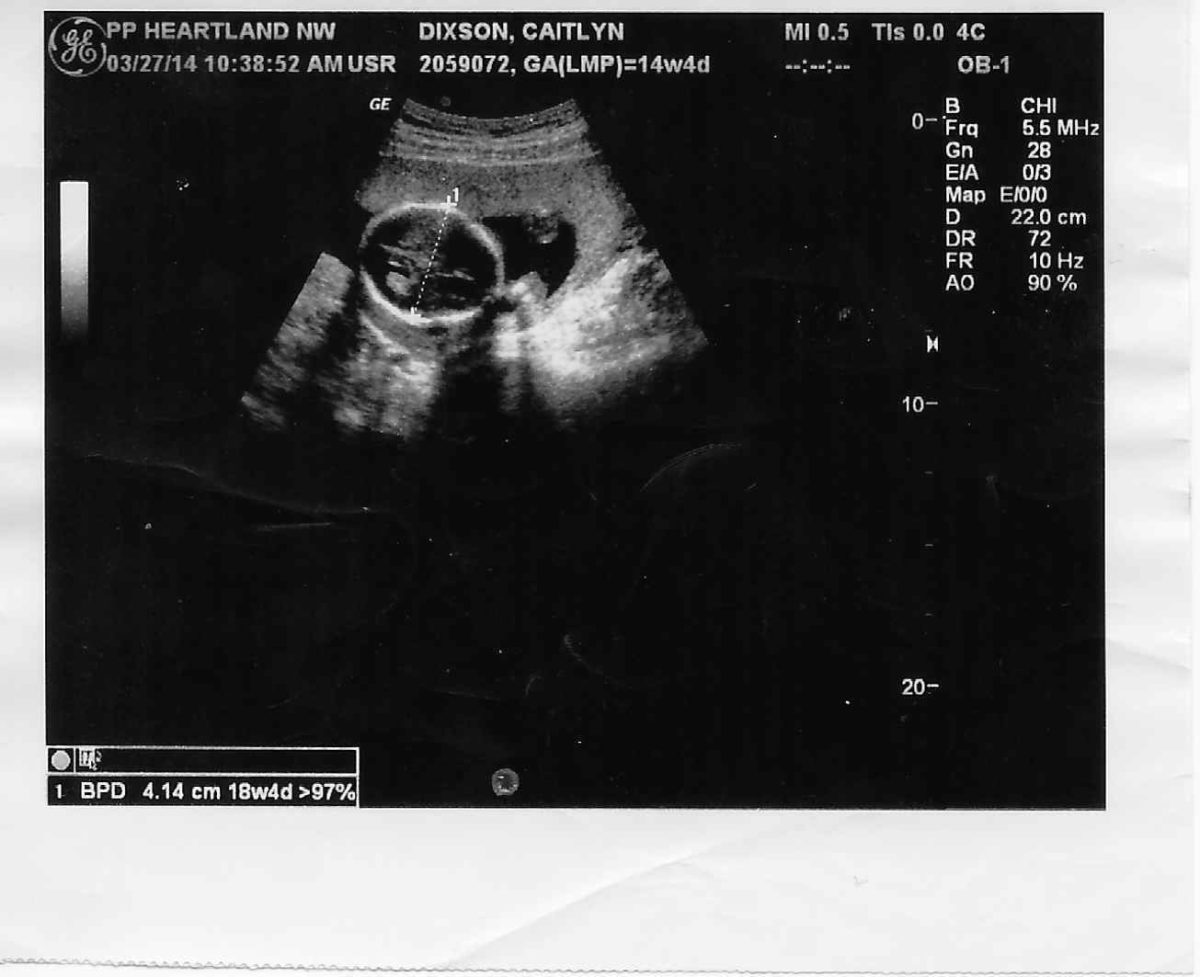

At Planned Parenthood, Dixson received an ultrasound. The ultrasound image, which Dixson has to this day, shows the top of her son’s head in order to measure the circumference for pregnancy-dating purposes. She couldn’t see her baby’s beating heart and rapidly forming limbs, his face or his fingers or toes. The fuzzy ultrasound image of the top of her son’s head does not even appear to be of a baby.